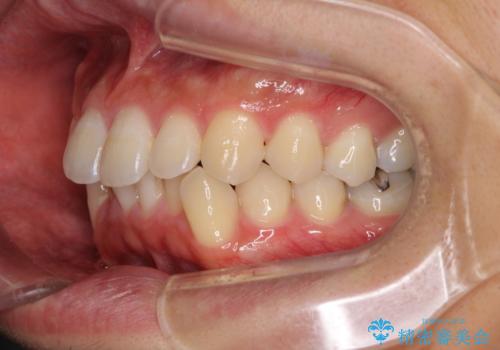

口が少し閉じにくい インビザラインによる非抜歯矯正

- 口元の突出感を治したいとのことで来院された患者様です。

上下顎ともにIPR(歯と歯の間を削る)と歯列全体の拡大によって口元が引っ込むように設計し、インビザラインにより治療を行うこととしました。

抜歯をして口元を下げなければならないほど出っ歯ではなかったため、少しずつ治療ゴールを変更しながら仕上げていきました。

気になっていた前歯の飛び出した印象は、最終的にはスッキリと引っ込み、大変満足していただきました。